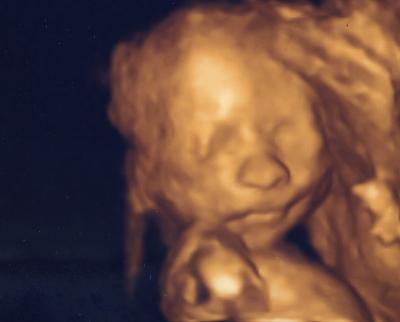

Guten Morgen Ihr Lieben, Heute morgen bin ich mit einem Dauergrinsen ins Büro gefahren. beim Organscreening im Krankenhaus kam nämlich heraus: alles in bester Ordnung, das Kind wird schön lange Beine haben und .... das beste überhaupt: es wird ein Mädchen..................!!!!!! Yeah - bin stolz wie Oscar. Und der Papa wird sich erst freuen - war auch sein größter Wunsch - eine kleine Prinzessin zu bekommen - bisher hat er nur Söhne gezeugt ( in seiner damaligen Ehe) Nun muss ich aber aufpassen mich nicht zu verplappern - er will es nämlich auf gar keinen Fall vorher wissen ... Also geniesst den Tag ebenso wie ich - hier scheint die Sonne - auch da draussen .... Ach Mensch natürlich auch das tolle 3D Bildchen - so langsam wird es zum Menschlein ... Liebe Grüße von der stolzen Bine

Bild zu grosses Organscreening und Outing - Forum für März - Mamis